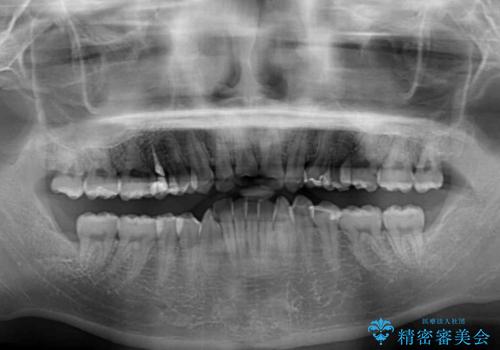

骨格的に、下顎が右側にずれており、左側の咬み合わせに鋏状咬合などのアンバランスが生じている状態でした。

また、上顎前歯に欠損が1本あり、上下ともに前歯部に叢生が認められ、下顎前歯の大半が隠れてしまうほどの過蓋咬合も認められました。

骨格的な左右差が大きかったため、上下の正中のズレや、左右奥歯の咬み合わせなどは妥協的な仕上がりとなりました。